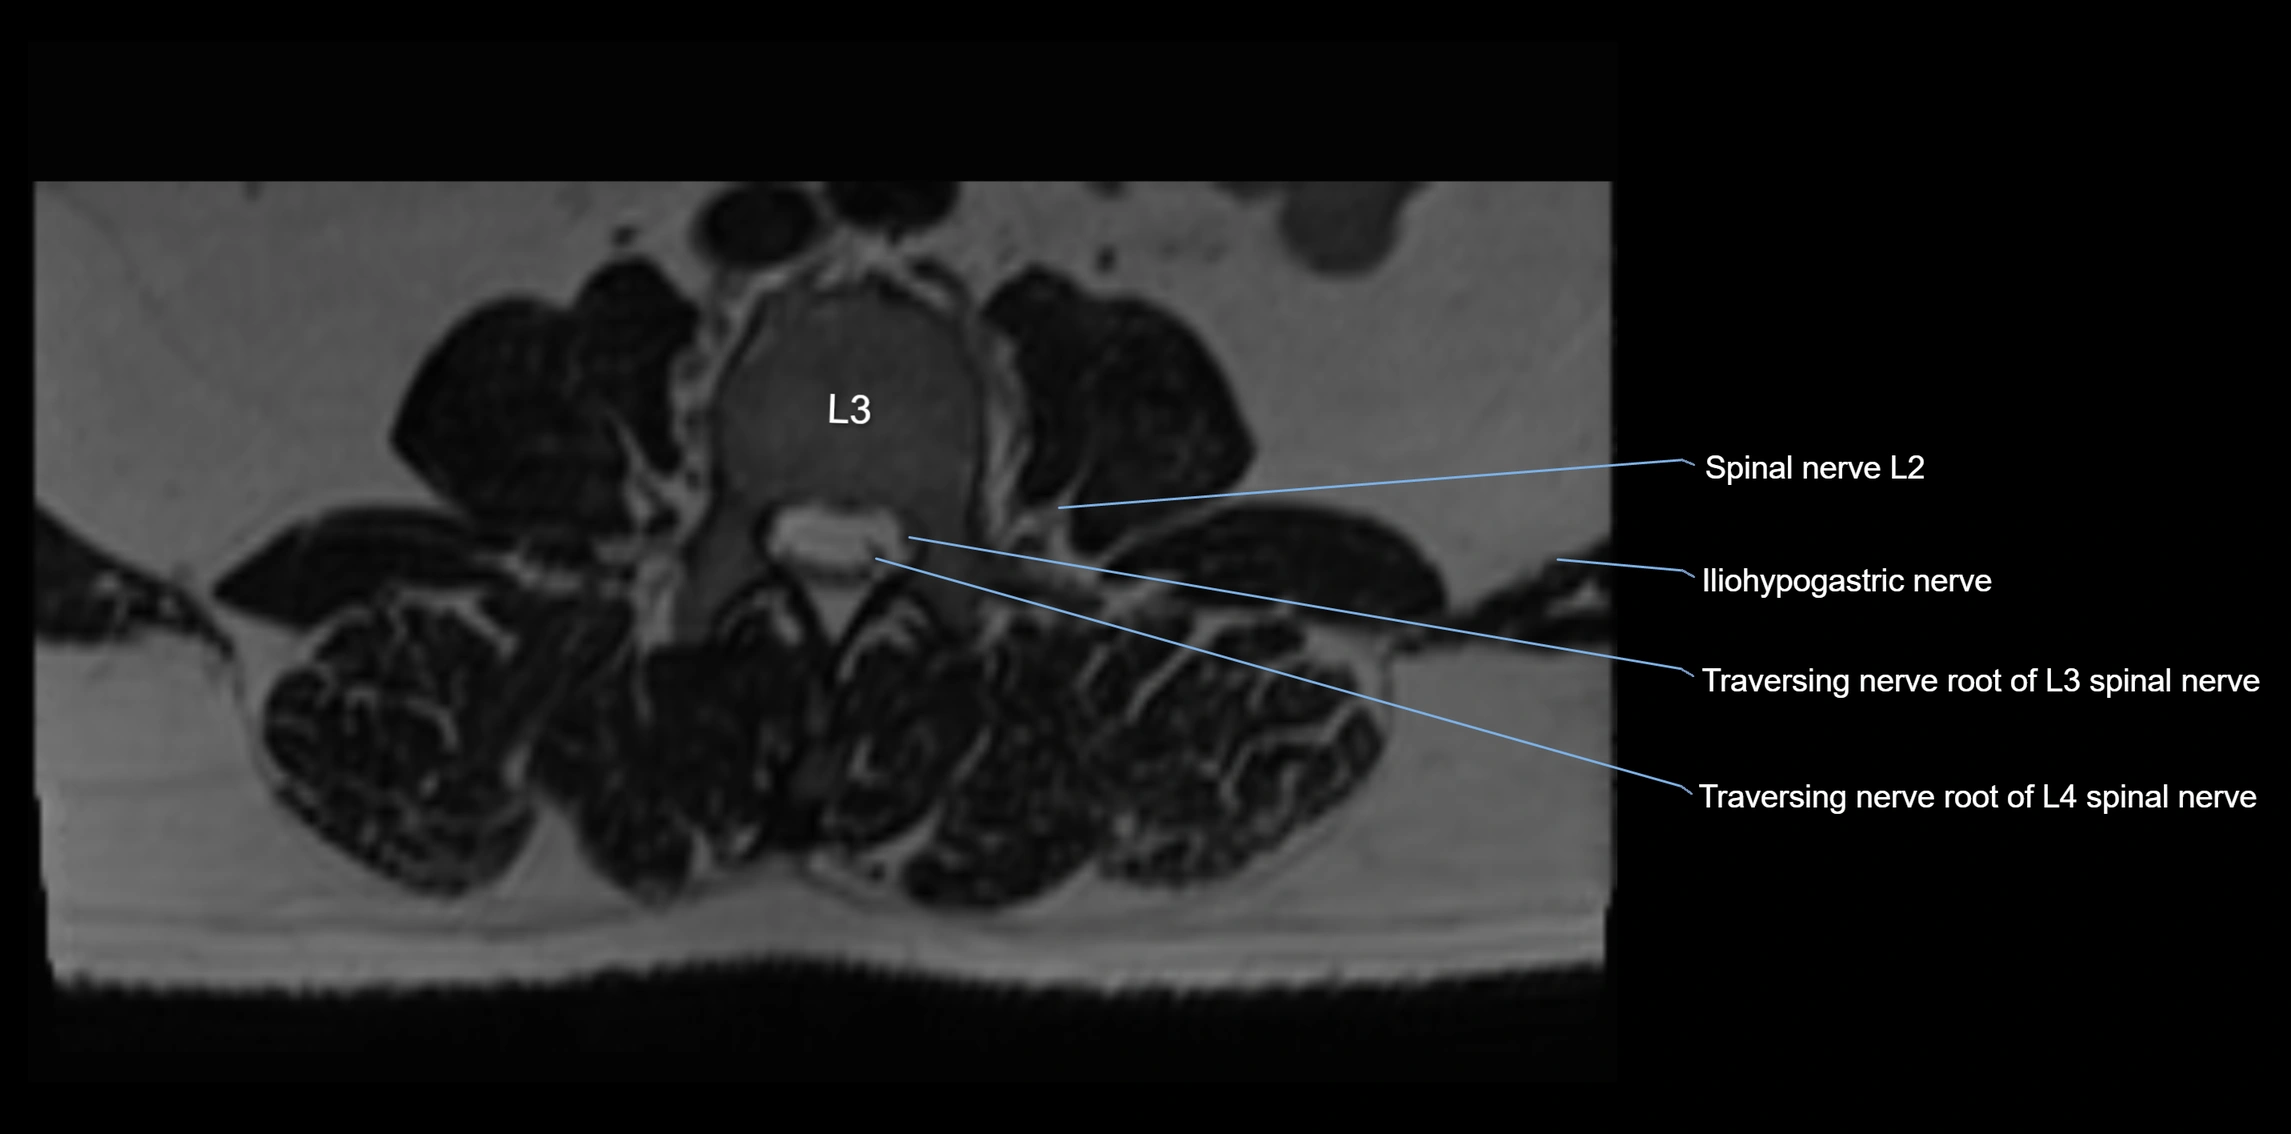

MRI Appearance

T1-weighted images:

• Nerve appears as a very thin low-to-intermediate signal intensity structure

• Surrounded by bright fat, aiding visualization

T2-weighted images:

• Nerve shows intermediate to mildly hyperintense signal compared to muscle

• Pathological involvement appears brighter

STIR (Short Tau Inversion Recovery):

• Normal nerve appears dark

• Inflamed or entrapped nerve appears bright hyperintense

T1 Fat-Sat Post-Contrast:

• Normal nerve enhances minimally

• Pathologic nerve (neuritis, entrapment, tumor infiltration) shows focal or diffuse enhancement

3D T2 SPACE / CISS:

• Nerve appears intermediate to mildly hyperintense compared to muscle

• Surrounded by bright fat or CSF, improving visualization

• Best sequence for mapping small pelvic nerves such as the anococcygeal